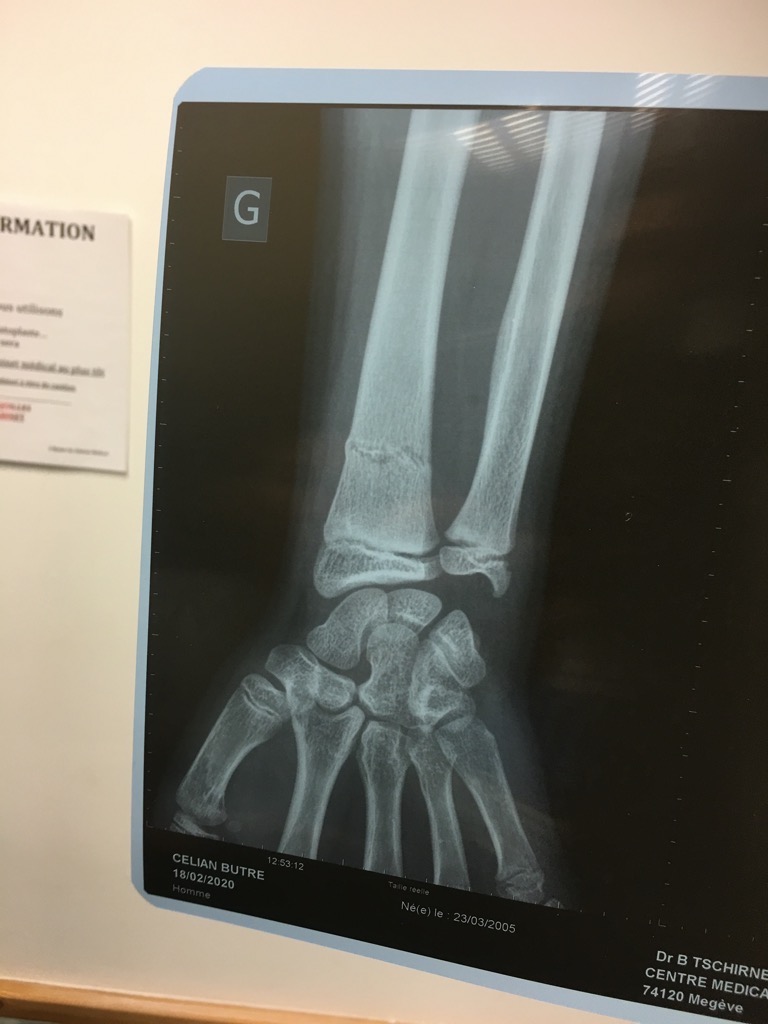

![]() Réduction de fracture au centre

medical de Mégève.

![]() Après un peu de gaz hilarant

|

Ben au moins maintenant, il n'y

a plus grand chose à faire à part réviser!